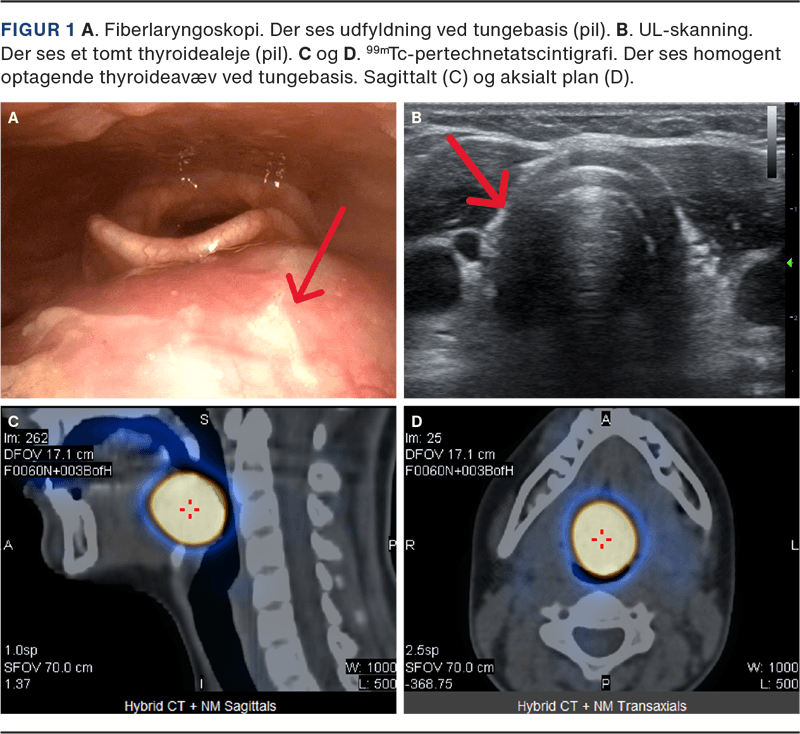

En dobbeltsidig rinoskopi og initial inspektion af cavum oris viste normale forhold. Ved fiberlayngoskopi observeredes en prominerende, velafgrænset, let asymmetrisk tumor ved tungebasis (Figur 1A). Efterfølgende sås, at tumor akkurat kunne visualiseres transoralt ved kraftig depression af tungen. En UL-skanning af halsen viste et tomt thyroidealeje, på hvilken baggrund man fik mistanke om, at det drejede sig om lingval thyroidea (Figur 1 B). Arbejdsdiagnosen bekræftedes ved en 99mTc-pertechnetat-scintigrafi, hvorpå der sås en solitær diffust opladende proces i tungebasis (Figur 1C). Paraklinisk var patienten eutyroid (normale niveauer af thyroideastimulerende hormon (TSH), T3, og T4). En thyroglobulinantistoftest var positiv, mens de øvrige thyroideaantistoffer (TPO og TRAB) var negative. Søvnmonitorering viste enkelte apnøer, uden desaturationer og et apnø-hypopnø-index på 2,5, hvilket er i normalområdet.

Den sande prævalens af lingval thyroidea er ukendt, idet tilstanden ofte er symptomfattig og kan forblive uerkendt. Lingval thyroidea forekommer 4-5 gange hyppigere hos kvinder end hos mænd. De typiske symptomer er bl.a. globulusfornemmelse, åndenød, hoste, synkebesvær, hæshed, snorken, apnø eller blødning. Patienten i sygehistorien havde få symptomer, som havde givet anledning til at opsøge en øre-næse-hals-læge. Tilstanden skal mistænkes ved fund af tumor ved tungebasis og fravær af glandula thyreoidea ved UL-skanning. Diagnosen bekræftes ved scintigrafi, som desuden kan afklare, om der er eventuelt yderligere aberrant thyreoideavæv [3]. Omkring 70% af patienterne udvikler over tid myksødem [4].